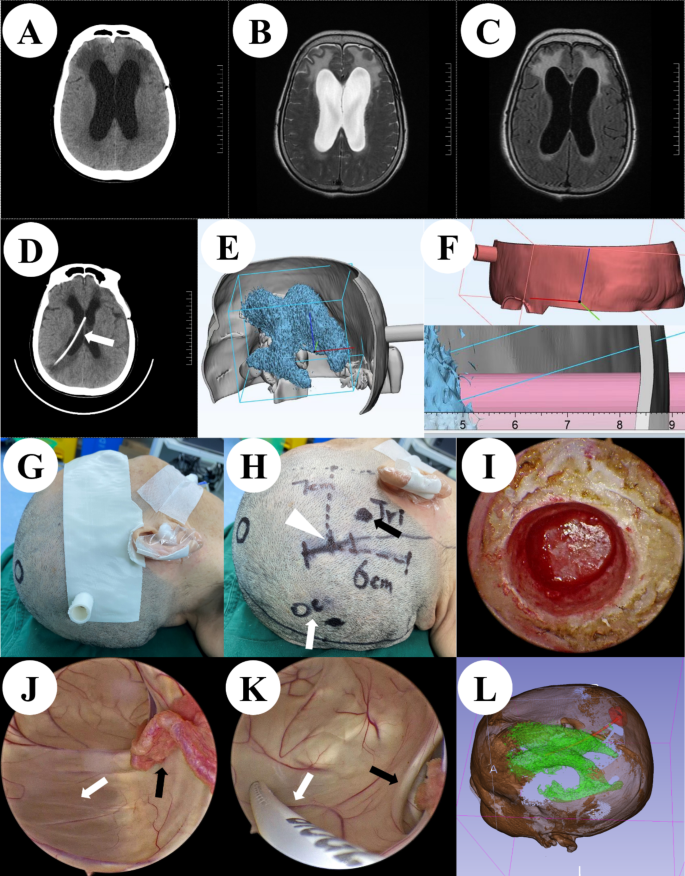

A 81 years old female patient, admitted to the hospital due to postoperative hydrocephalus after intracranial aneurysm surgery. The patient has a previous history of intracranial aneurysm rupture and craniotomy clipping surgery. The patient had clear consciousness upon admission, but had poor mental state and delayed reactions. Figure 2 shows the patient’s preoperative brain CT/MRI(Fig. 2A-C), postoperative brain CT(Fig. 2D), preoperative 3D Slicer reconstruction (Fig. 2E-F) and 3D printing guide plate positioning images(Fig. 2G-H), intraoperative neuroendoscopic images(Fig. 2I-K), and postoperative 3D Slicer reconstruction virtual reality images(Fig. 2L).

(A) Preoperative brain CT. (B,C) Preoperative brain MRI. (D) Postoperative brain CT with arrow indicating shunt tube. (E) Virtual reality graphics reconstructed using 3D Slicer before surgery. (F) 3D positioning guide plate virtual reality graphics. (G) Preoperative positioning based on 3D printing guide plate. (H) Minimally invasive incision, white triangle represents the “Cai’s point”, black arrow represents the puncture point in the triangle area, and white arrow represents the puncture point in the occipital angle. (I) Keyhole approach. (J) In the lateral ventricle under neuroendoscope, the black arrow represents the choroid plexus, and the white arrow indicates the septum pellucidum structure. (K) Insertion of ventricular shunt tube under direct vision of neuroendoscopy(White arrow), the black arrow represents the interventricular hole. (L) Postoperative reconstruction of lateral ventricle and drainage tube with 3D Slicer.